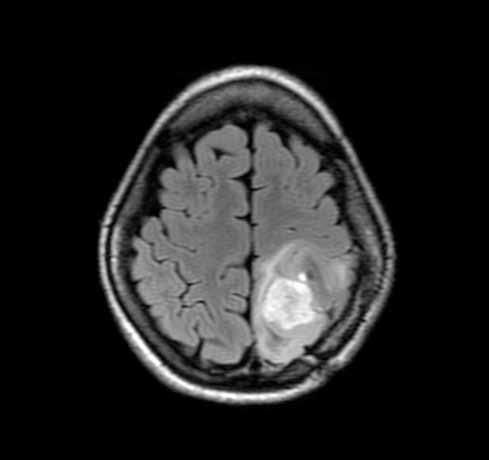

Joshua B. Bederson, MD, Chairman of the Department of Neurosurgery, describes how a powerful new imaging technology will give neurosurgeons a crystal clear advantage.

“on the left is an image of a brain, obtained before surgery and viewed midoperation, using our current technology. neurosurgeons rely on images like this during surgery to navigate through the brain, but such technology conveys a relatively limited amount of information and cannot account for changes that occur during the operation. now look at the right: an image of the same patient obtained with more advanced techniques and showing important motor fibers that control movement of the arm and leg. the difference is dramatic but this technique is not accessible at the most critical moment, during the operation, and cannot be updated in real time as the operation proceeds.

“soon the department of neurosurgery will be equipped with advanced technology to see the brain in mid-operation with the same level of detail as we do before and after surgery, and to account for shifts in the position and shape of the brain that occur during surgery. a collaboration with one of the industry’s leading companies and the department of neuroradiology, the technology uses sophisticated gPs-like navigation devices, sliding gantry intraoperative imaging, 3d angiography, and other components that allow neurosurgeons to view— in real time—the results of the procedure. the benefits for patients are immediately clear.

“Mount sinai will be one of the first medical centers in the country to combine this technology with intraoperative biplane cerebral angiography. we already have some of the best neuroimaging specialists in the nation; now we’ll have the intraoperative technology to match that expertise.”